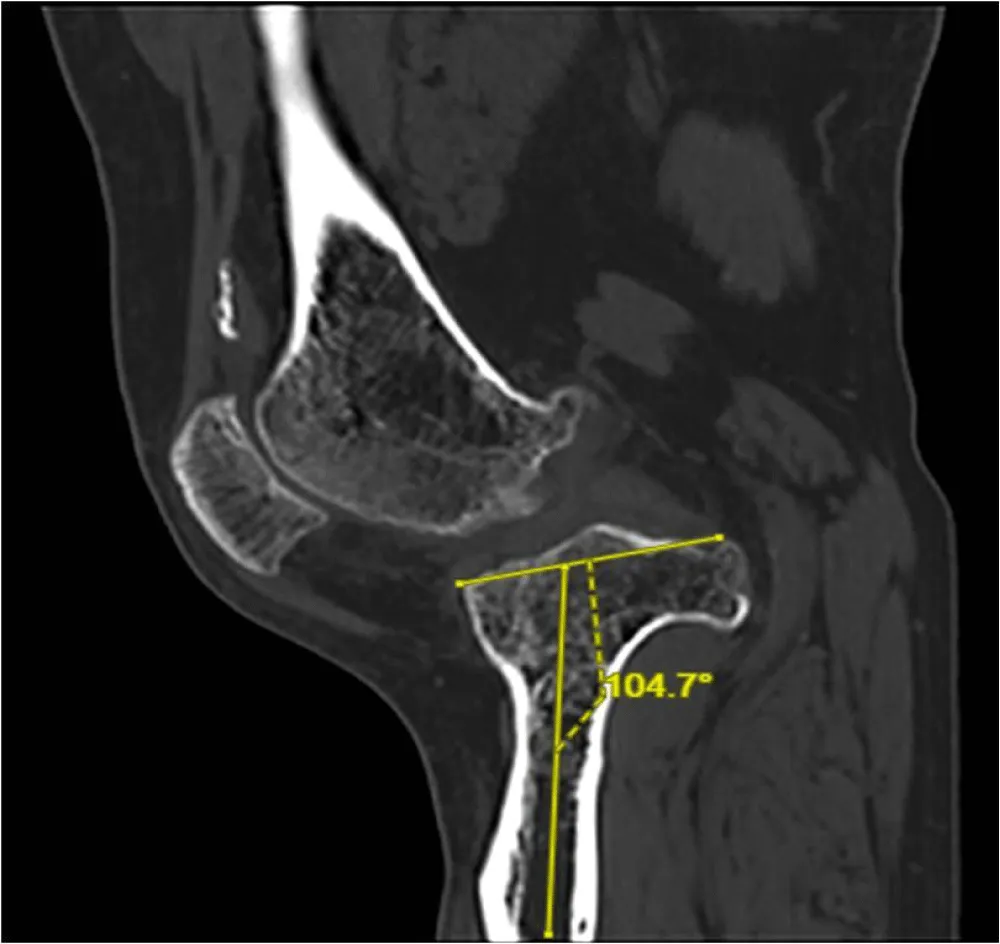

X-rays reveal severe deforming osteoarthritis of the right knee with a medial tibial metaphyseal angle of 53.6° (Figure 1). Telemetry shows medialization of the weight-bearing axis of the right lower extremity due to severe genu varum (Figure 2). Computed tomography (CT) confirms joint destruction with varus deformity of the proximal tibia (Figure 3), and severe misalignment of the posterior tibial slope (Figure 4).

There are several surgical options for addressing knee deformities in patients with achondroplasia, including TKA without correcting mild deformities or correcting significant misalignments in one or two stages. Varus alignment of the knee can be caused by tibial deformities, combined tibiofemoral deformities, or ligament imbalances. Understanding the malalignment is essential in TKA to restore the neutral mechanical axis in the frontal plane. The most common knee morphotype in achondroplasia patients is genu varum with widened metaphyses. Occasionally, extra-articular metaphyseal varus angulation may be linked to lateral collateral ligament insufficiency and flexion contractures, which can restrict range of motion. Therefore, technical challenges in TKA for these patients include soft tissue contractures, ligament laxity, extra-articular deformities, and difficulties with standard prosthesis sizing due to bone size and joint structural abnormalities. It is widely agreed that CT scans are crucial for preoperative planning in these cases, helping assess bone mass, deformities, and implant sizes to ensure proper prosthetic component fit in the femur and tibia medullary canals. Custom implants are often necessary in cases of skeletal dysplasia.